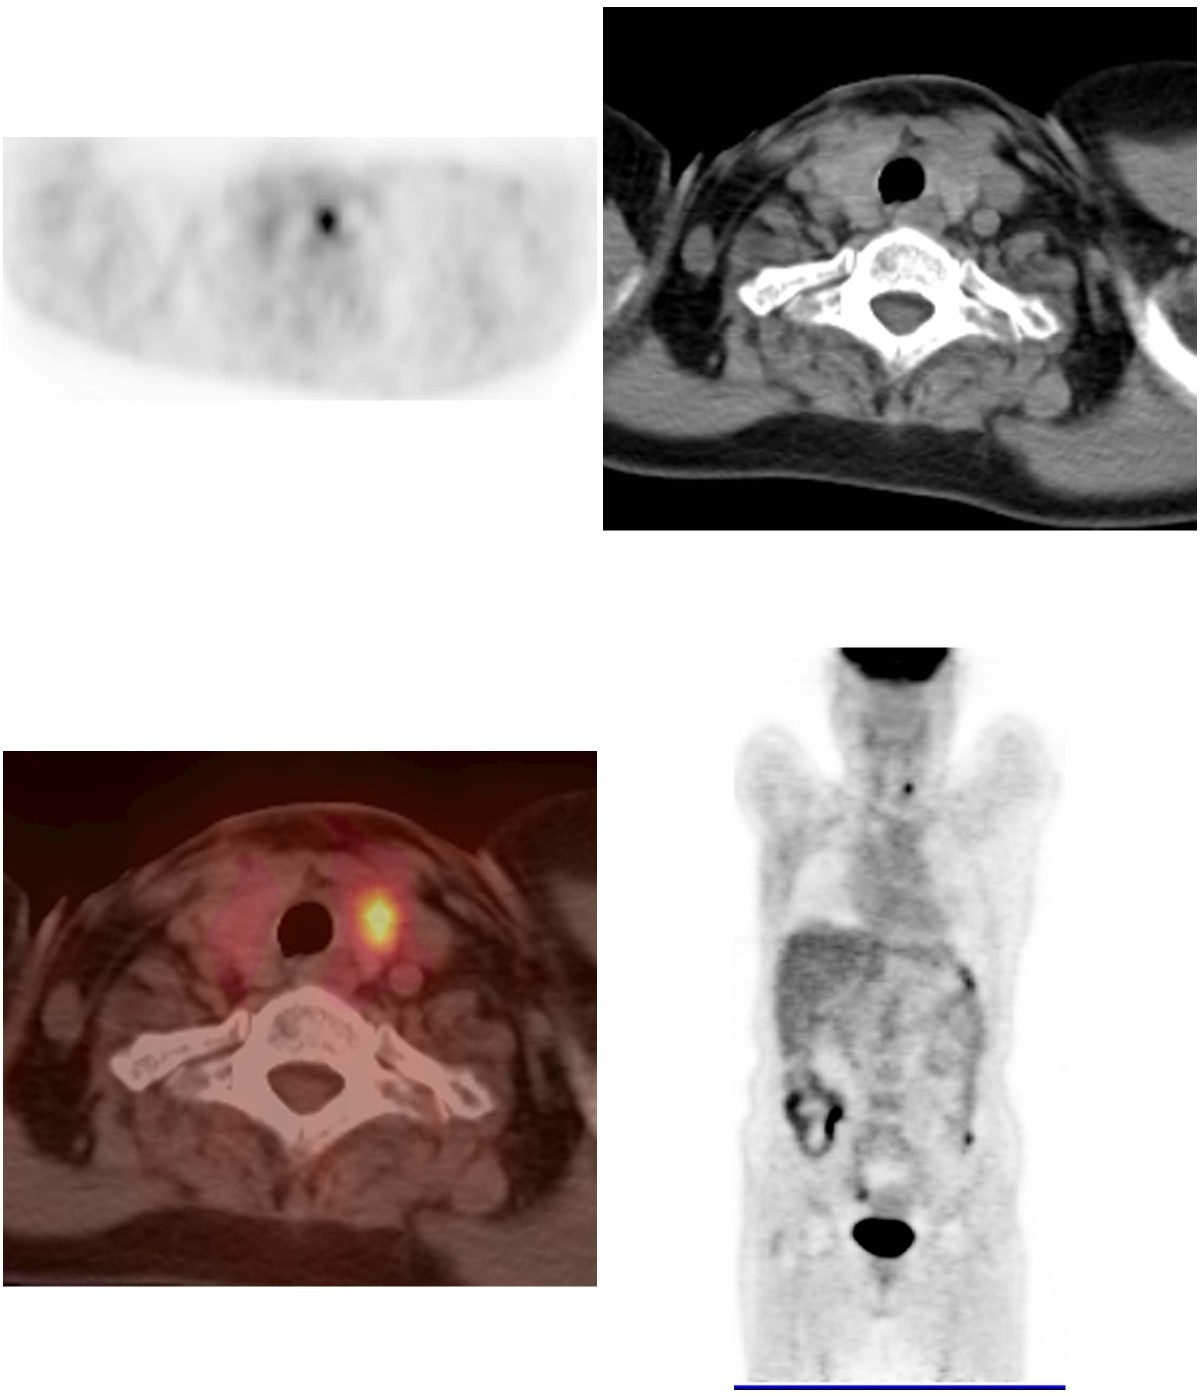

Incidental Detection of Follicular Thyroid Carcinoma in 68GaPSMA PET Pet Scan Lights Up Thyroid Learn about the different types of thyroid disease, such as hypothyroidism and hyperthyroidism, and how they affect your. Although fdg pet does not provide information beyond that yielded by ultrasound for local preoperative assessment of thyroid cancer [], several studies have reported that it has a high. Identify the role of pet/ct in the management of thyroid cancer. Diffuse thyroid. Pet Scan Lights Up Thyroid.

PETCT scan showing (a) hypermetabolic enlarged thyroid gland, (b Pet Scan Lights Up Thyroid Treatment protocols for advanced thyroid cancer have expanded in the past several years due to the increasing availability of targeted. Identify the role of pet/ct in the management of thyroid cancer. Hyperthyroidism is a condition of excessive thyroid hormone production that can cause various symptoms such as weight loss, anxiety, and heart. Learn about the different types of thyroid disease,. Pet Scan Lights Up Thyroid.